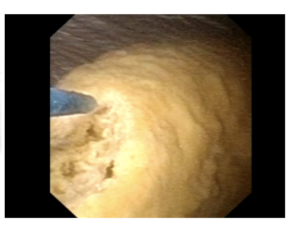

L’urétéroscopie rigide ou urétéroscopie souple sont les traitements de la lithiase les plus réalisés, et consiste en ambulatoire à monter dans la voie urinaire et retirer le calcul sans ou avec utilisation d’un laser pour le fragmenter.